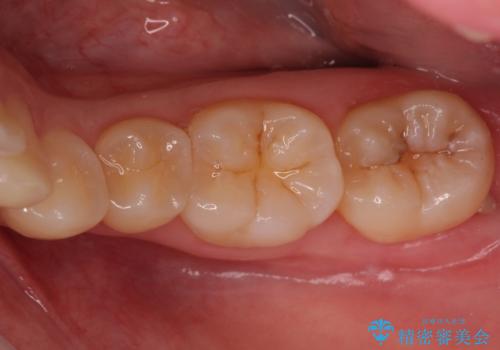

奥歯の虫歯 セラミックインレーでの治療

- 下の奥歯の黒ずみが気になるとのことで来院されました。

検査の結果咬む面に虫歯があることがわかりました。

削る前は小さな虫歯に見えますが、歯の中で進行しつつある虫歯でした。

虫歯が大きくなると必要な治療が増えてえしまうため早期発見、早期治療を行うことが大事になってきます。